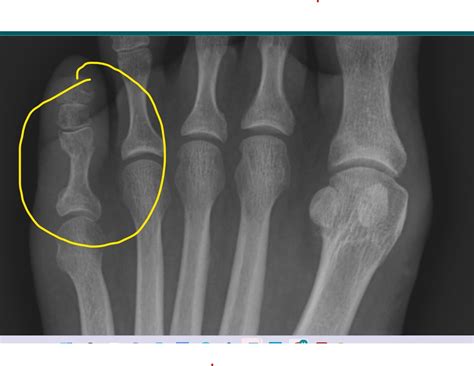

• Imaging Tests: X-rays are the primary imaging tool used to diagnose bone fractures. They can provide clear images of the bone structure, allowing the healthcare provider to determine the type and extent of the fracture. In some cases, additional imaging tests such as CT scans or MRI may be required for a more detailed assessment.

For instance, a young athlete with a stress fracture in the foot may require a different treatment approach compared to an elderly individual with a nondisplaced fracture in the wrist. The athlete may benefit from a combination of rest, physical therapy, and gradual reintroduction of activities, while the elderly individual may need additional support to manage pain and mobility issues.